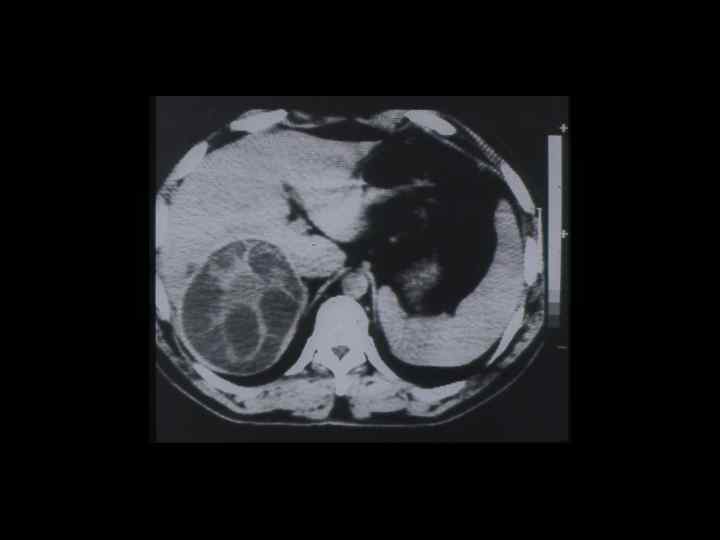

АКТУАЛЬНЫЕ ВОПРОСЫ РЕНТГЕНОЛОГИИ ЛУЧЕВАЯ ДИАГНОСТИКА ОЧАГОВЫХ ПОРАЖЕНИЙ ПЕЧЕНИ КАВЕРНОЗНАЯ ГЕМАНГИОМА Компьютерно-томографическая семиотика: - ограниченный участок пониженой плотности (до 50 -30 ед Н) - границы могут быть ровными, но нечеткими - после введения РКВ - характерный феномен усиления плотности от периферии к центру в течении нескольких минут после внутривенного введения РКВ

Клиническое наблюдение. Пациентка С. , 1953 г. р.